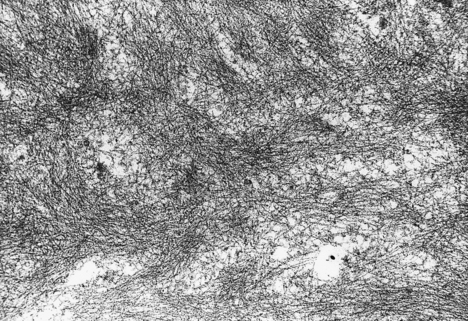

fibrillar ultrastructure (Fig. 7.13)

Fig. 7.13 Amyloid ultrastructure. Amyloid substances are characterised by a fibrillar appearance on electron microscopy.